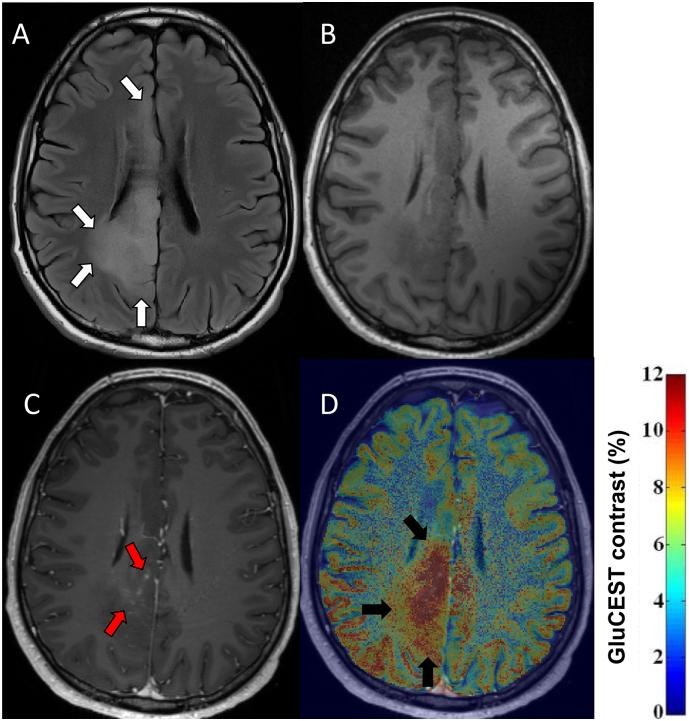

We applied the glutamate-weighted imaging method GluCEST (glutamate chemical exchange saturation transfer) and single voxel MRS (magnetic resonance spectroscopy) at 7 Telsa (7 T) to patients with gliomas. GluCEST contrast and MRS metabolite concentrations were quantified within the tumour region and peritumoural rim. Clinical variables of tumour aggressiveness (prior adjuvant therapy and previous radiological progression) and epilepsy (any prior seizures, seizure in last month and drug refractory epilepsy) were correlated with respective glutamate concentrations. Images were separated into post-hoc determined patterns and clinical variables were compared across patterns.

Ten adult patients with a histo-molecular (n = 9) or radiological (n = 1) diagnosis of grade II-III diffuse glioma were recruited, 40.3 +/- 12.3 years. Increased tumour GluCEST contrast was associated with prior adjuvant therapy (p = .001), and increased peritumoural GluCEST contrast was associated with both recent seizures (p = .038) and drug refractory epilepsy (p = .029). We distinguished two unique GluCEST contrast patterns with distinct clinical and radiological features. MRS glutamate correlated with GluCEST contrast within the peritumoural voxel (R = 0.89, p = .003) and a positive trend existed in the tumour voxel (R = 0.65, p = .113).